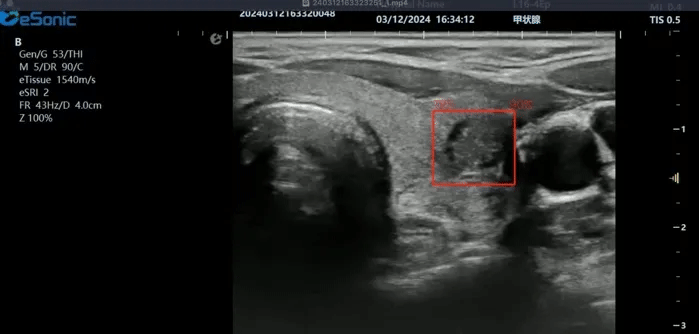

3377体育医疗(ESI)表示,其最新的人工智能功能可以帮助到医疗机构的工作效率,功能包括,实时、动态、快速自动识别病灶,良恶性病灶概率预测,甲状腺结节和乳腺的二维灰阶动态自动实时检测需求,提供多个结节动态检测轮廓框。实时获取多幅具备临床特征(大小、属性等)的结节切面,同时提供当前切面所示结节的结节大小、属性特征、TI-RADS 分级。

对于甲状腺结节相关的自动检测功能,甲状腺结节病灶检出率≥95%,良恶性分类灵敏度≥90%、良恶性分类特异度≥85%。

对于乳腺结节相关的自动检测功能,乳腺结节病灶检出率≥95%、良恶性分类灵敏度≥90%、良恶性分类特异度≥85%。